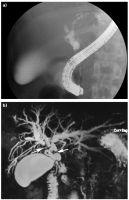

Cholangitis

Abbildung 4a-b: Primär sklerosierende Cholangitis im fortgeschrittenen Stadium. (a) Die ERCP kann lediglich die distale Striktur darstellen, nicht jedoch die intrahepatischen Gallenwege. (b) Die MRCP zeigt die ausgeprägten Strikturen intra- und extrahepatisch (Pfeile) mit deutlicher Cholangiektasie.